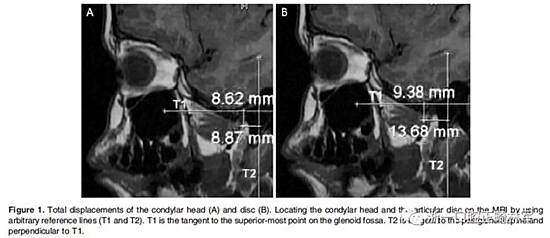

在生理休息位和另外三個位置獲得了四個咬合蠟型,這三個位置是水平前伸0mm時的HA1,水平前伸5mm時的HA2以及水平前伸7.5mm時的HA3。所有三個位置均保持垂直高度為5mm。病人分別將四個蠟型咬在嘴里,接受了5次連續(xù)磁共振掃描。外部標記的Frankfort水平面保持垂直于掃描臺。標記髁突頭和關節(jié)盤的位置,并在整個研究過程中對它們的位置變化進行描繪(Figure 1和2;1Table 1和2)。